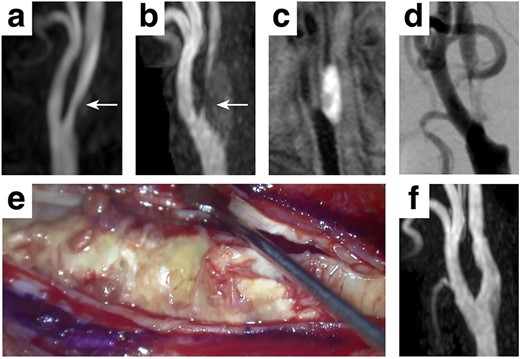

A 77-year-old Japanese male with a past medical history of acute cardiac infarction was diagnosed with a right carotid artery stenosis which progressed in three years (Fig. 1a and b, white arrows). The carotid plaque showed a high signal intensity on the T1-weighted image (T1WI), suggesting a vulnerable plaque containing intraplaque hemorrhage (Fig. 1c). A digital subtraction angiogram revealed a 93% internal carotid artery stenosis according to the North American Symptomatic Carotid Endarterectomy Trial (NASCET) starting at the carotid bifurcation (Fig. 1d). The patient was elected for carotid endarterectomy rather than carotid artery stenting, considering the surgical risks accompanying the presumed vulnerable plaque [5]. However, during the presurgical assessment, an echocardiogram showed a decreased left ventricular ejection fraction accompanied by bright myocardium and left atrial dilatation, suspicious of cardiac amyloidosis. Myocardial pathological examination by a myocardial biopsy achieved a final diagnosis of ATTRwt amyloidosis. Carotid endarterectomy was performed uneventfully, and the patient was discharged 9 days after surgery with a modified Rankin Scale 0 (Fig. 1f).

Clinical presentation A mild stenosis at the right carotid artery (white arrows, a) progressed in 3 years (white arrows, b), requiring surgical intervention. The carotid plaque showed a high signal intensity on T1WI (c) with 93% stenosis assessed by the NASCET criteria (d). A standard carotid endarterectomy was performed (e) without any complication (f).